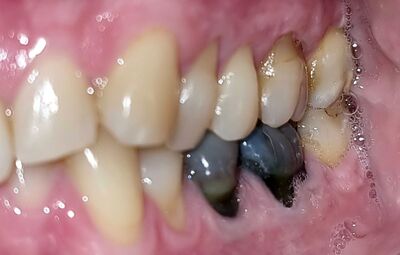

Goldkrone 6c4a72f3

Bereits Anfangs des letzten 20. Jhd. hat Dr. William Hunter in seiner damals revolutionäre Arbeit "Die Rolle von Sepsis und Antisepsis in Medizin" beschrieben, wie die Goldkrone ein Risiko darstellen kann:

Die Goldkrone als "ein Mausoleum von Gold über eine Masse von Sepsis".

Leider gilt diese Aussage nicht nur für überkronte sondern für alle wurzelbehandelten Zähne. Jeder solcher Zahn ist langfristig (Jahre bis Jahrzehnte!) ein Risiko für die Gesundheit. Dank Fortschritte in der analytischen Chemie, vor allem durch die Arbeiten von Prof. Boyd Haley sind wir heute in der Lage, solche Risikofaktoren rechtzeitig zu erkennen.